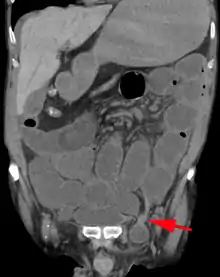

An incarcerated inguinal hernia as seen on cross sectional CT scan

A frontal view of an incarcerated inguinal hernia (on the patient's left side) with dilated loops of bowel above.